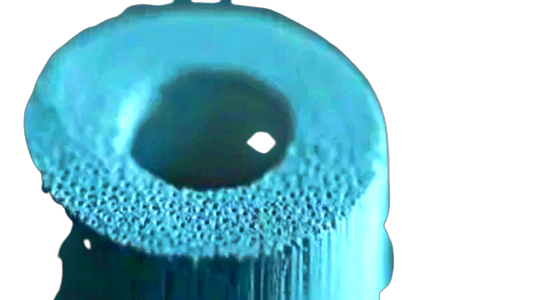

Il legno di rattan per riprodurre la composizione chimica e l’architettura porosa dell’osso umano. Il rivoluzionario dispositivo arriva nelle nostre sale operatorie grazie all’accordo tra Abiogen Pharma, azienda farmaceutica italiana nel settore da cinque generazioni, e GreenBone Ortho Spa che ha sviluppato e brevettato il sostituto osseo. Massimo Di Martino, Presidente e Amministratore Delegato di Abiogen Pharma: “Siamo molto contenti di questa partnership con un’azienda italiana leader nell’innovazione dei bio- materiali ortopedici che è Green bone ortho spa. Per noi è molto importante perché consolida la nostra presenza in questa area terapeutica. Noi vogliamo rimanere un riferimento a 360° e soprattutto in questo caso andiamo anche a estendere la nostra proposta nell’ambito della chirurgia ricostruttiva dei difetti ossei. E’ evidente che è una soluzione fortemente innovativa con grandi standard di efficacia e di sicurezza che può permettere di superare i limiti e venivano imposti dai sostituti ossei di vecchia generazione”.

Di qui l’accordo con GreenBone che garantisce ad Abiogen la distribuzione del dispositivo in esclusiva su tutto il territorio nazionale. Derivato dalla trasformazione biomorfica del legno di rattan, palma che cresce in Africa e Asia, il dispositivo offre soluzioni efficaci ispirandosi alla natura. Spiega Prisca Di Martino, International Business Unit Head, Abiogen Pharma: “In natura esistono alternative utilizzabili che replicano la struttura dell’osso come ad esempio il corallo però per costi possibilità di approvvigionamento e dimensioni finiscono per non essere la soluzione ideale. In questo caso la soluzione proposta da GreenBone è un sostituto osseo che riproduce la composizione chimica e l’architettura porosa 3D dell’osso naturale partendo dal legno di rattan. Il legno infatti, così come l’osso, deve essere leggero ma allo stesso tempo sostenere certo peso e permette il flusso dei liquidi”.

Ancora la Di Martino: “Ecco questa struttura è la trasformazione biomorfica del legno di rattan ne fanno un device estremamente innovativo con determinati vantaggi :parliamo di proprietà di osteointegrazione, di osteoconduzione, ma soprattutto osteoinduzione. Questo significa che permette la formazione di nuovo tessuto osseo che si va a sostituire al device: stesso questa tecnologia permette la produzione in qualsiasi dimensione e forma del prodotto in modo tale da risolvere problemi ed esigenze cliniche che il chirurgo ortopedico riscontra quotidianamente. Inoltre ha il vantaggio di poter essere direttamente modellato dal chirurgo in fase operatoria e quindi permette di andare a realizzare il prodotto in modo che sia estremamente adattabile al difetto osseo in questione cosa molto vantaggiosa e importante perché spesso la reale forma e la dimensione del difetto osseo si scopre solo durante la fase operatoria”.